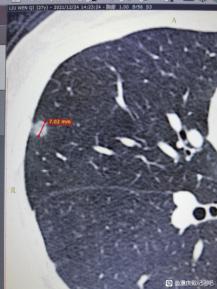

戴主任您好,我相信没有人喜欢在网上暴露自己的疾病,诉说自己的无助,但是恐惧、无助、不解,真的会摧毁一个人所有的尊严。在三个月前偶然体检,体检出纯磨玻璃结节5*6mm,-359hu。三个月之后湘雅做ct,已经变成了7*7mm混合磨玻璃结节,怀疑4b类,并且多发良性小结节。其实直到现在,我都很难接受,觉得自己拖累家人,拖累新婚的老公,我不抽烟不喝酒,也不知道为什么这个病能找到我。

按理来说,今年的元旦应该是非常幸福的,因为我所在的湖南下雪了。作为一名四川人,第一次在城里看到下雪,还在跟老公堆雪人、打雪仗。但当我拿到自己的ct报告单时,犹如一盆冷水直接浇到了我的头上:双肺多发小结节,右中肺7×7mm混合磨玻璃结节,纵膈见团片状阴影,大概2.1cm×1.3cm。